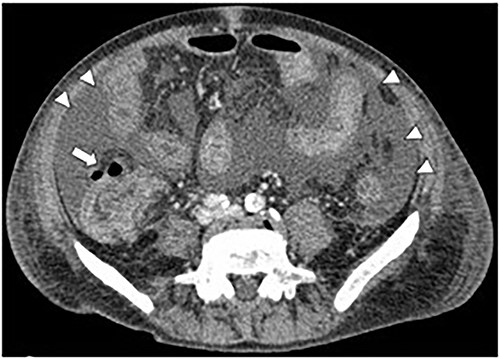

A 71-year-old man was diagnosed with advanced non-small cell lung carcinoma and pleura and lymph node metastasis. He received carboplatin, paclitaxel, bevacizumab and atezolizumab every 3 weeks as first-line chemotherapy for 4 months. As the pleural dissemination worsened, docetaxel and ramucirumab were administered as second-line treatment. The patient had three episodes of ileocecal diverticulitis following chemotherapy, all of which were treated conservatively with antimicrobials and fasting therapy. The diverticulitis episodes and computed tomography (CT) images are shown in Figs 1 and 2a–c. During the fourth diverticulitis episode, the patient presented with fever and abdominal pain, worsening after 5 days. Physical examination revealed tenderness and rigidity throughout the abdomen. Vital signs were stable, but body temperature was 37.7°C. Laboratory data showed inflammation with a white blood cell (WBC) count of 21 400/μL and a C-reactive protein (CRP) level of 23.8 mg/dL. Abdominal CT imaging showed ascites and intra-abdominal free air around the right-side colon (Fig. 3). Hence, we suspected a right-side colon perforation with acute diffuse peritonitis and performed an emergency laparotomy with a midline incision. Surveying the small bowel revealed that ileal perforation occurred only a few centimeters proximal to the ileocolic valve (Fig. 4). The patient underwent ileocecal resection, ileostomy and a colonic mucous fistula.